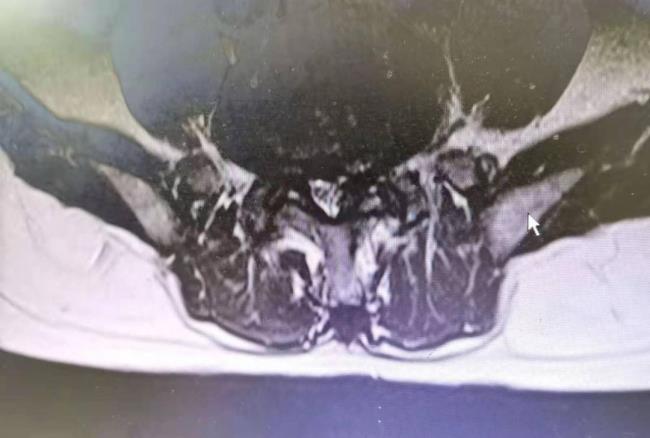

吴叔今年63岁,7年前曾因患腰椎间盘突出症,到我院康复医学科治疗,经康复医学科廖庆辉主任予针灸、推拿等综合治疗后,吴叔的腰腿痛症状得以缓解,此后多年一直未复发。今年6月吴叔因搬重物后再次出现腰臀部疼痛,右下肢麻木等症状,吴叔再次到我院康复医学科就诊。经廖庆辉主任诊断后,确诊为腰椎间盘脱出症,并腰椎管狭窄症,普通的物理综合治疗收效甚微,但吴叔拒绝手术,坚决要求保守治疗。面对患者的坚持态度,廖庆辉主任通过对吴叔的病史采集、全面检查及辅助检查后决定用科室新的中医微创技术“内热针”对其进行治疗。整个治疗耗时半小时左右,过程顺利。第二天吴叔的疼痛麻木症状明显缓解。行第二次内热针治疗后,6月30日吴叔的腰腿痛及麻木症状祛除出院。